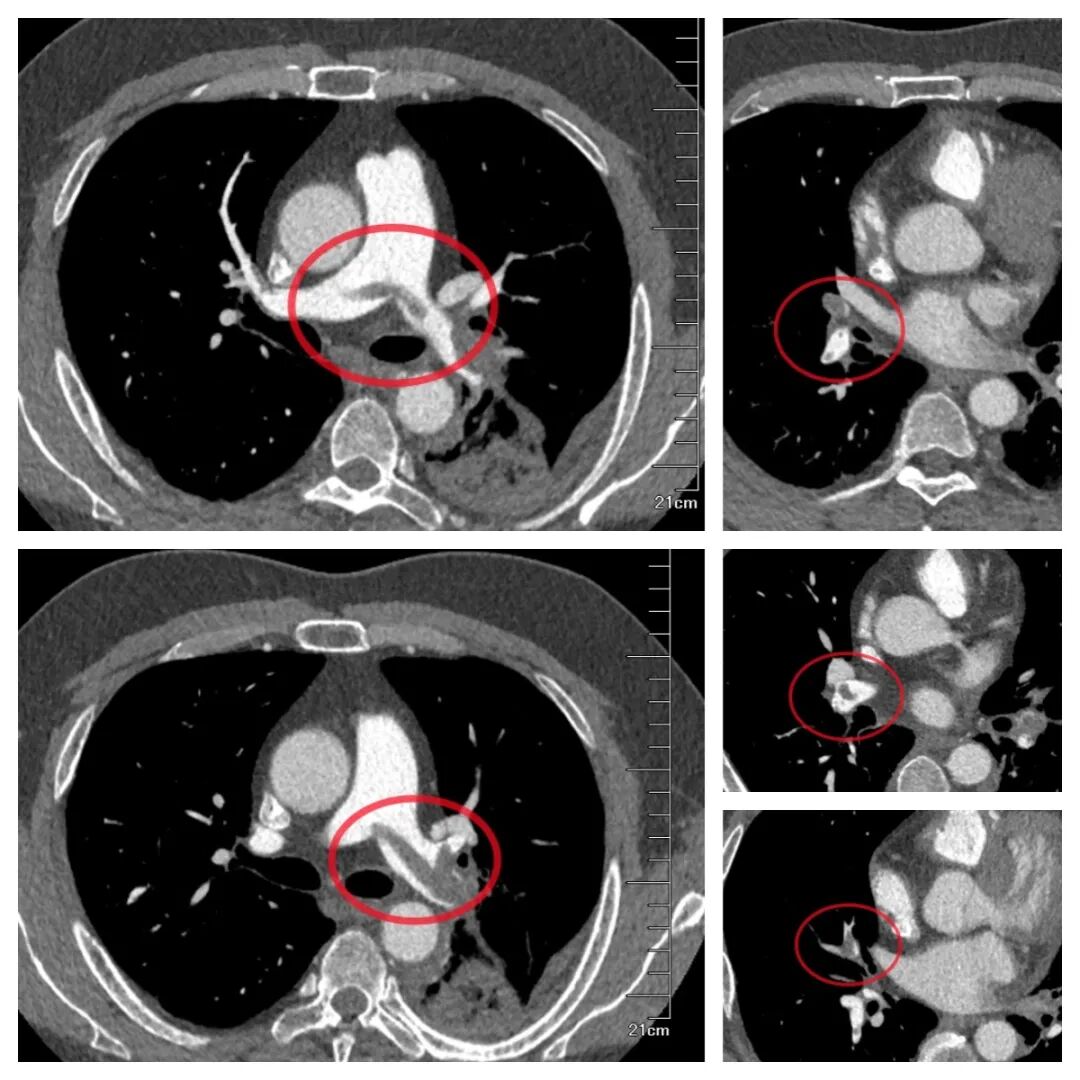

小伙因“感冒”就医,医生敏锐识破致命肺栓塞!精准介入取栓碎栓,成功化解“夺命危机”

近期,青岛市妇女儿童医院介入医学团队凭借敏锐的判断和精湛的技术,不仅成功挽救了这名青年患者的生命,还接连救治了多名突发肺栓塞的孕产妇,守护了母婴安全。